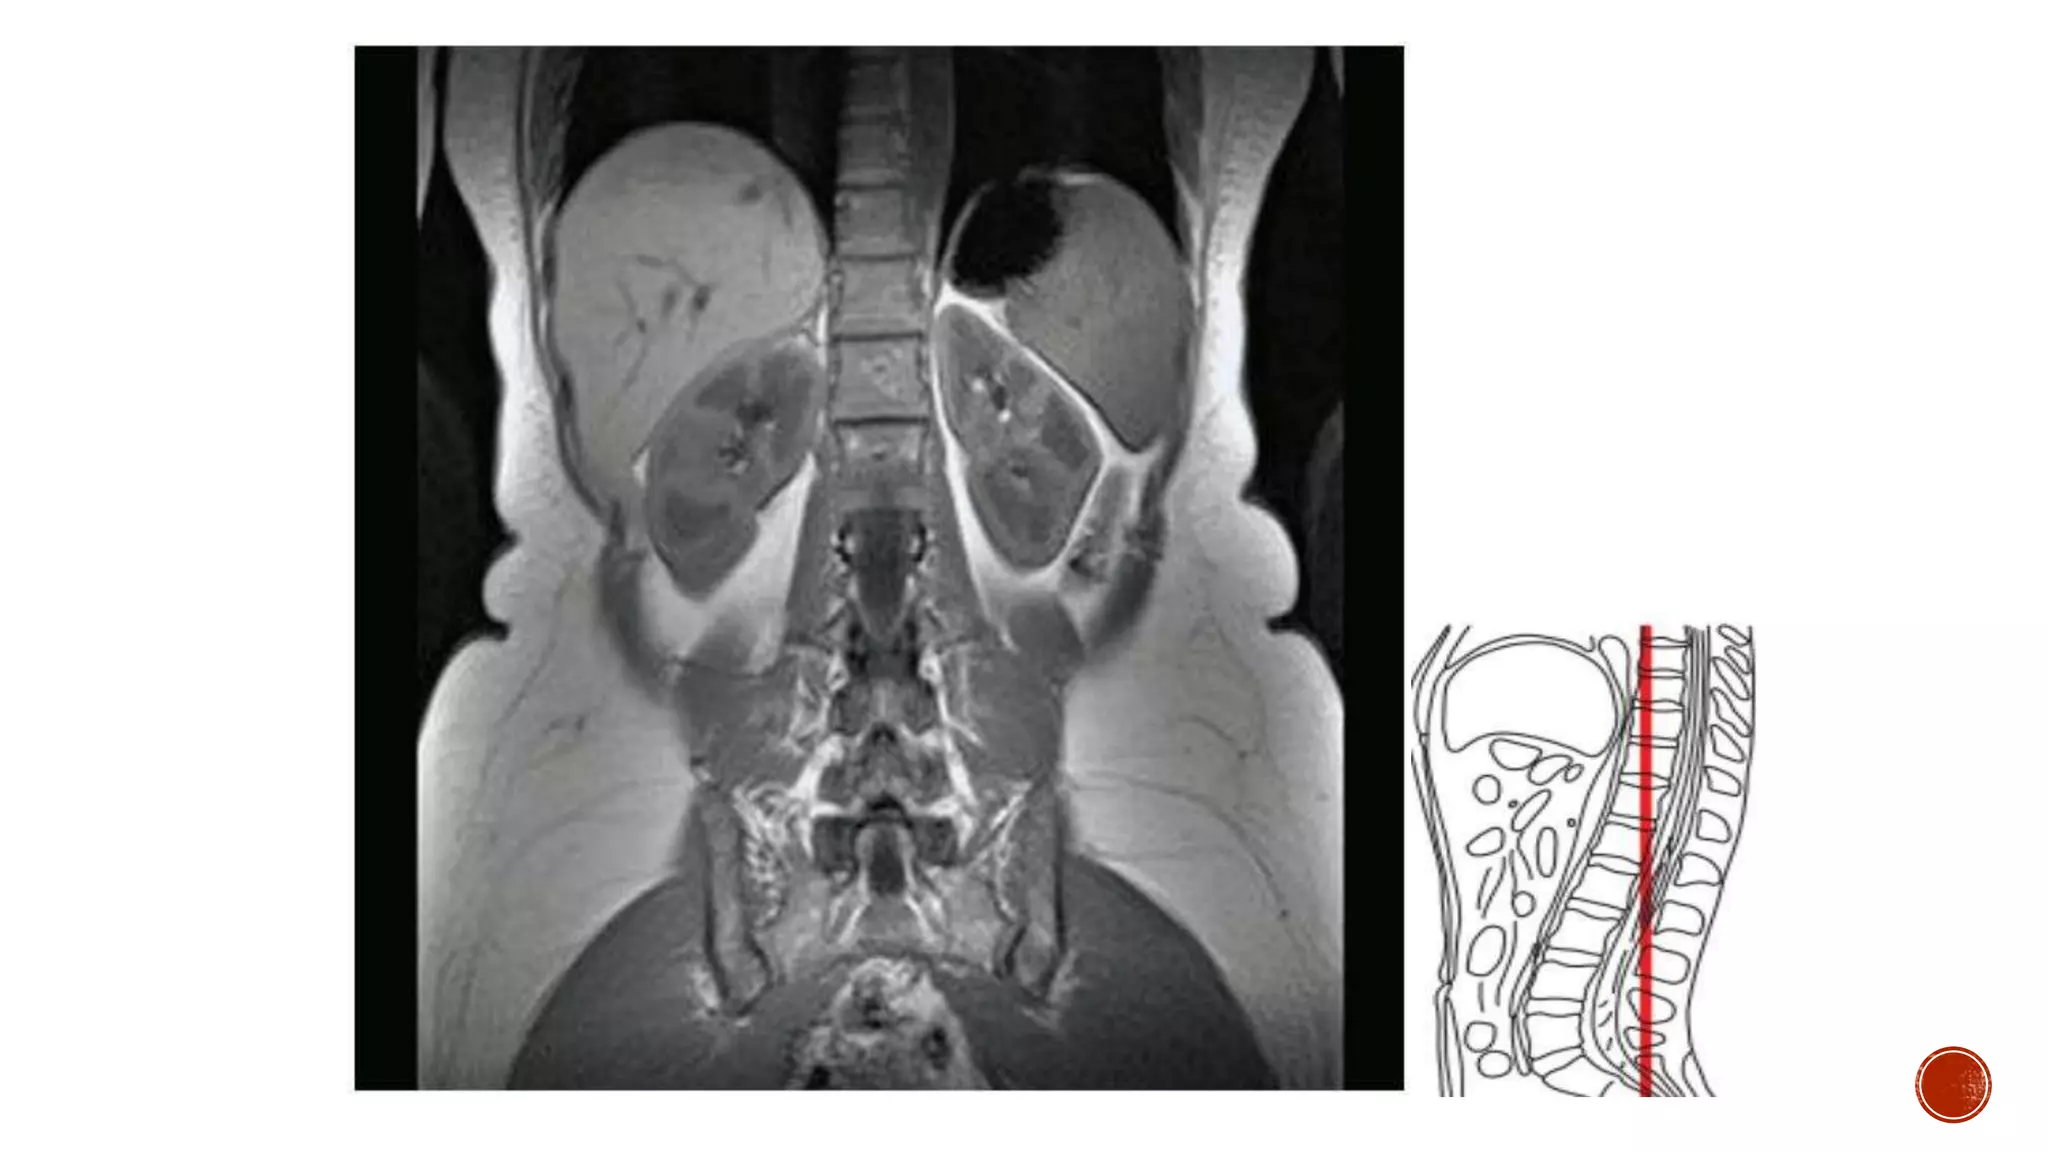

The document describes the anatomy of the abdomen and pelvis region of the human body. It lists over 40 structures and their locations, including major organs like the liver, kidneys, intestines, blood vessels and muscles of the abdominal wall and pelvis. The structures are grouped into sections focusing on different anatomical areas like the abdomen, retroperitoneum, pelvis and gluteal region.